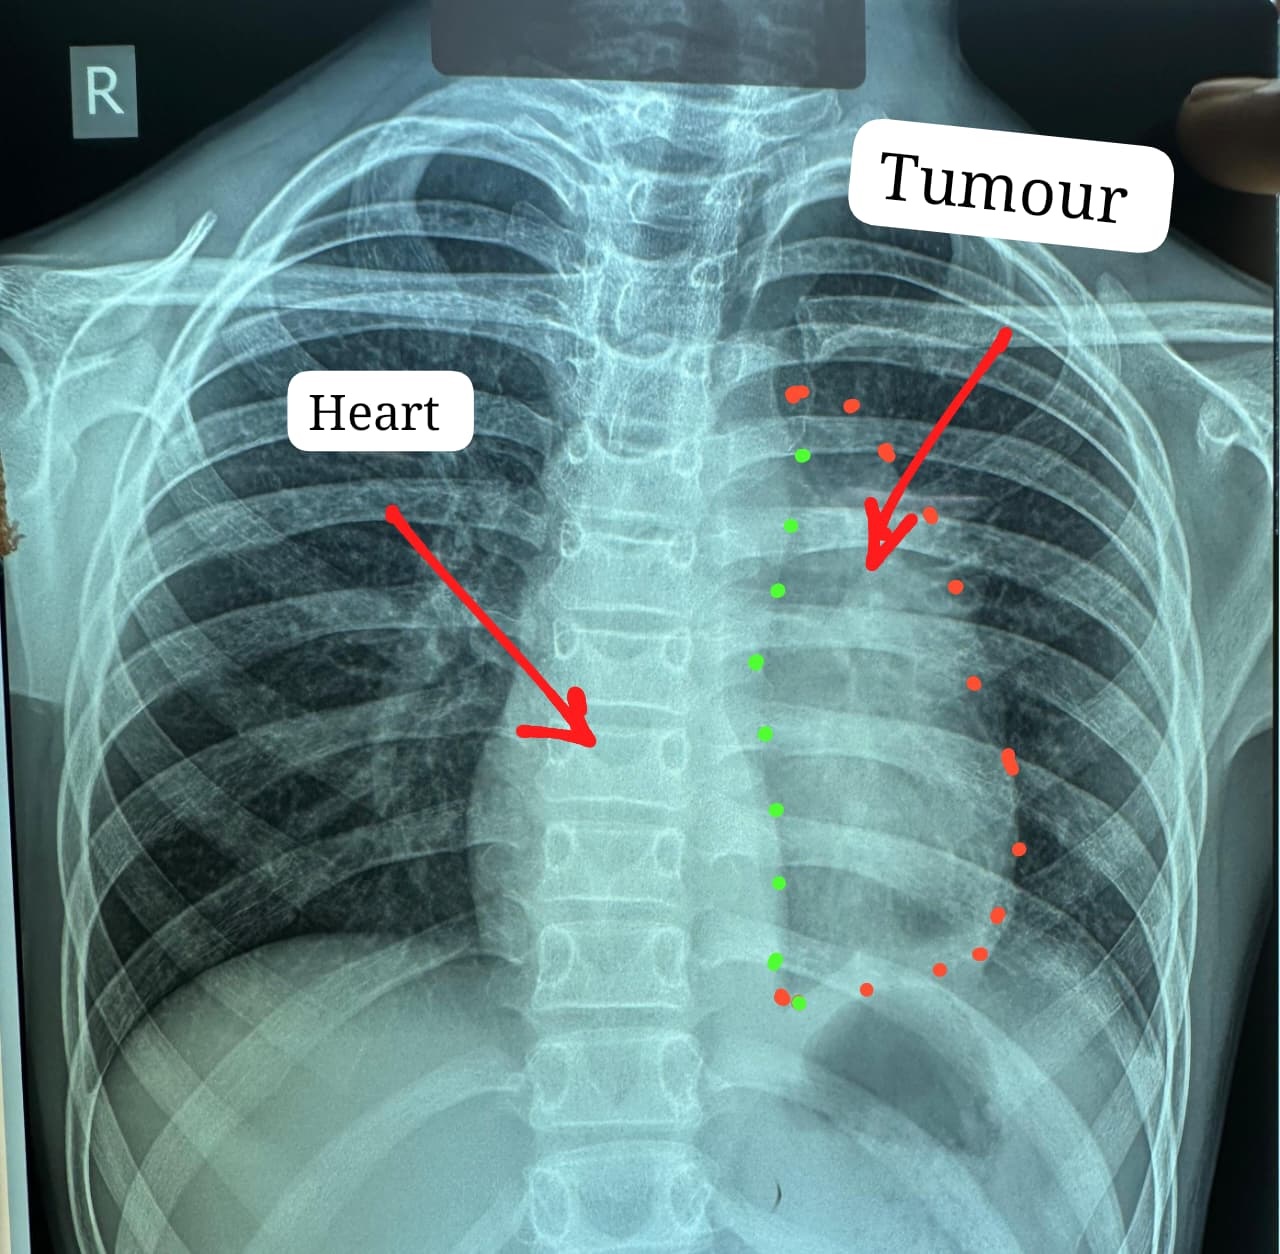

डॉक्टरों के अनुसार यह ट्यूमर सामान्यतः 40 से 60 वर्ष के लोगों में पाया जाता है और बच्चों में इसका मिलना अत्यंत दुर्लभ है। यह ट्यूमर हृदय, पेरिकार्डियम, फ्रेनिक नर्व महाधमनी (एओर्टा), मुख्य पल्मोनरी आर्टरी, लेफ्ट एट्रियम और फेफड़े से चिपका हुआ था। ऐसे मामलों में ट्यूमर को पूरी तरह निकाल पाना (आर-0 रिसेक्शन) लगभग असंभव माना जाता है, लेकिन अस्पताल में उपलब्ध हार्ट-लंग मशीन की मदद से यह संभव हो पाया।

मुख्य ट्यूमर के अलावा फेफड़े की प्लूरल कैविटी में फैले तीन अन्य सैटेलाइट ट्यूमर को भी सावधानीपूर्वक निकाला गया, ताकि भविष्य में कैंसर दोबारा फैलने की संभावना न रहे। निकाले गए ट्यूमर का आकार लगभग 12x8 सेंटीमीटर और वजन करीब 400 ग्राम था।